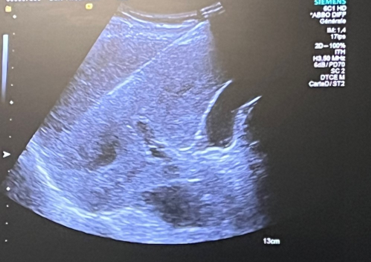

Cette technique est particulièrement efficace pour les tumeurs de petite taille, et elle est réalisée sous guidage radiologique par des techniques d’imagerie comme l’échographie, ou le scanner (CT).

- Le repérage de la cible à traiter en échographie ou au scanner. Une injection de produit de contraste pourra être réalisée si elle est jugée nécessaire. En fonction des conditions anatomiques et notamment des structures avoisinants le nodule, il est parfois nécessaire d’écarter ces structures à risques afin de les protéger de la zone de traitement. On parle de « dissection ». Elle peut être réalisée avec du gaz ou des liquides, grâce à une petite aiguille elle-même insérée au travers de la peau entre le nodule à traiter et l’organe ou la structure à protéger.

- La mise en place d’une ou plusieurs aiguilles de thermoablation au sein du nodule tumoral, au travers de la peau, sous guidage de l’imagerie.